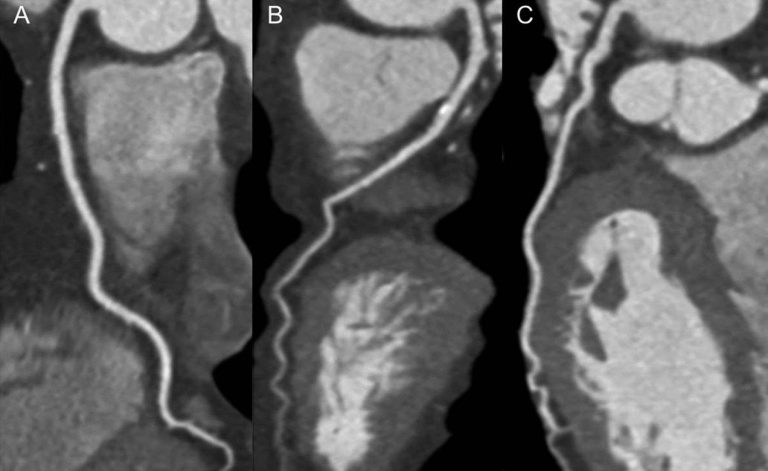

تصوير القلب المقطعي التاجي (CCTA)

هذا هو نوع من التصوير المقطعي المحوسب (CT) الذي يمكن أن يساعد في تشخيص مرض الشريان التاجي. يعطي صورة ثلاثية الأبعاد لغرف القلب والشرايين التاجية التي تمد القلب بالدم. CCTA هو اختبار غير جراحي للأشخاص الذين قد يعانون من أعراض قلبية غير عادية.